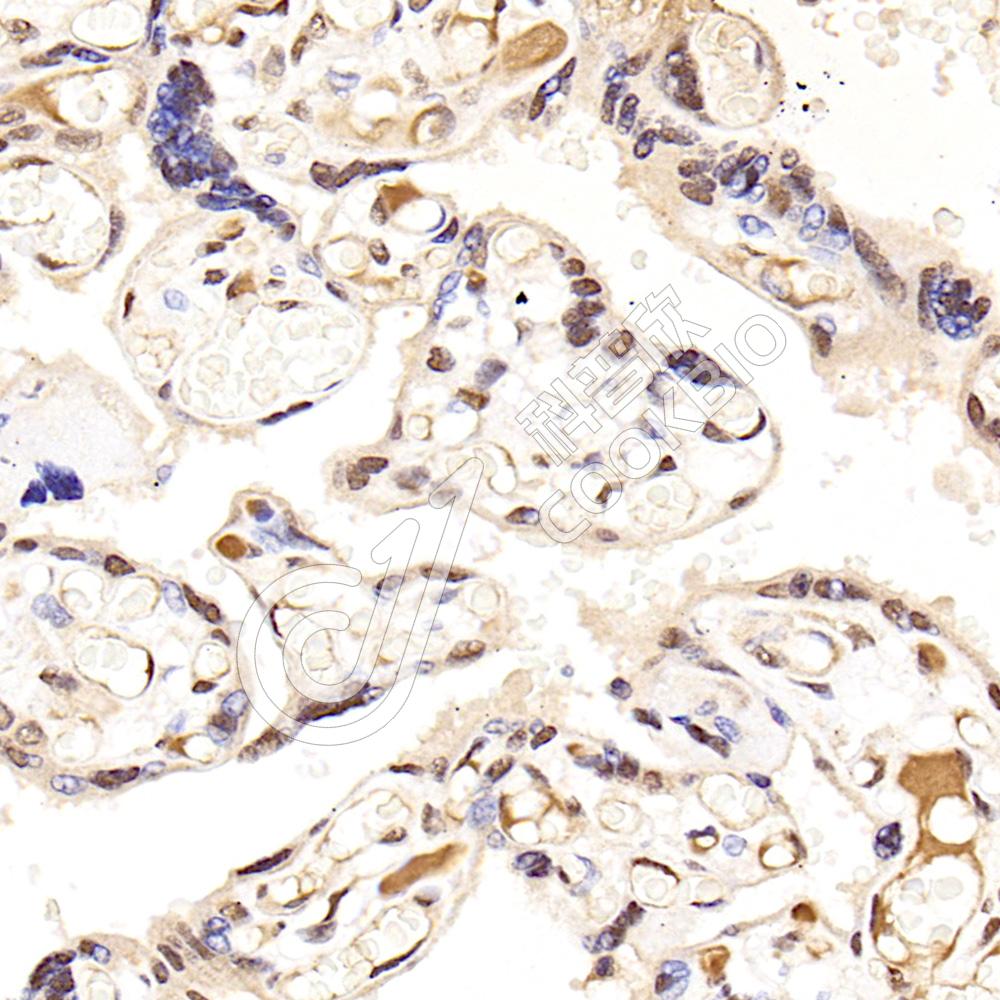

IHC检测CPSF73蛋白(货号 K1342312).

样品: 人胎盘, 4%多聚甲醛 (货号KSG1101) 固定12-24小时.

抗原修复: 柠檬酸抗原修复液(干粉, pH 6.0) (KSG1201), 98℃, 20分钟.

—抗: 1: 1500稀释, 4℃ 孵育过夜.

二抗: S-vision免疫组化多聚二抗(山羊抗兔),即用型 (货号KB3906), 室温孵育20分钟.